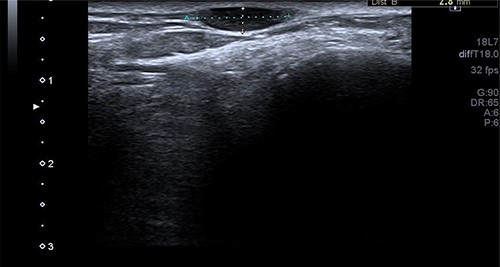

A 34-year-old gentleman presented with a swelling over the posterolateral aspect of his right ankle close to the Achilles tendon. He complained of pain and sensitivity to wearing shoes. The swelling was 10 × 5 mm, mobile and ultrasound (US) scan reported it as ‘A well-defined ovoid hypoechoic lesion underneath the skin surface measuring approximately 11 mm × 3 mm in diameter and appears related to a linear hypoechoic structure’ (Fig. 1). ‘The lesion is slightly heterogeneous in texture and shows posterior acoustic enhancement on the underlying tissues. There is mild internal vascularity of this lesion on Doppler assessment’ (Fig. 2) and ‘these appearances are suggestive of superficial neuroma lesion’. Post-excision, the histology of a single piece of pale smooth firm tissue (9 × 6 × 5 mm) was reported as angioleiomyoma. He made an uneventful recovery and was discharged after 4 months of follow-up.

The US scan image of the right ankle posteriolateral aspect of Patient 1, which showed a well-defined ovoid hypo echoic lesion underneath the skin surface; measuring ~11 × 3 mm in diameter.

An arteriogram or Doppler study may be useful to an extent, but a confirmed diagnosis is only obtained through histopathological examination after excision [8–10]. Case 1 had an US scan of the swelling which showed a well-defined ovoid hypoechoic lesion underneath the skin surface, and the lesion was slightly heterogeneous in texture and shows posterior acoustic enhancement on the underlying tissues. There was mild internal vascularity of this lesion on Doppler assessment—appearances suggestive of superficial neuroma lesion. The usual appearance of these lesions on USS is a well-circumscribed oval mass with a homogenous echotexture and occasionally hypoechoic protrusions.